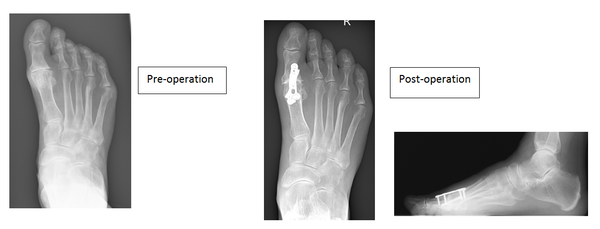

Joint fusion (Arthrodesis)

This operation is generally considered to be the gold standard and is definitive with regard to alleviating pain at the expense of all joint movement.

This is offset by fusing the great toe in slight elevation allowing you to rock through the toe, studies have shown improved weight bearing through the foot following this procedure.

It involves removing both surfaces of the joint and aligning the big toe to allow comfortable walking. The new position is maintained with screws and plates allowing the two bones to join together.

The fixation rarely troubles patients but the plate and screws can be removed if required. The main risk with this procedure is a non-union and the literature suggests around a 6% chance of it happening.

Pre and post diagram